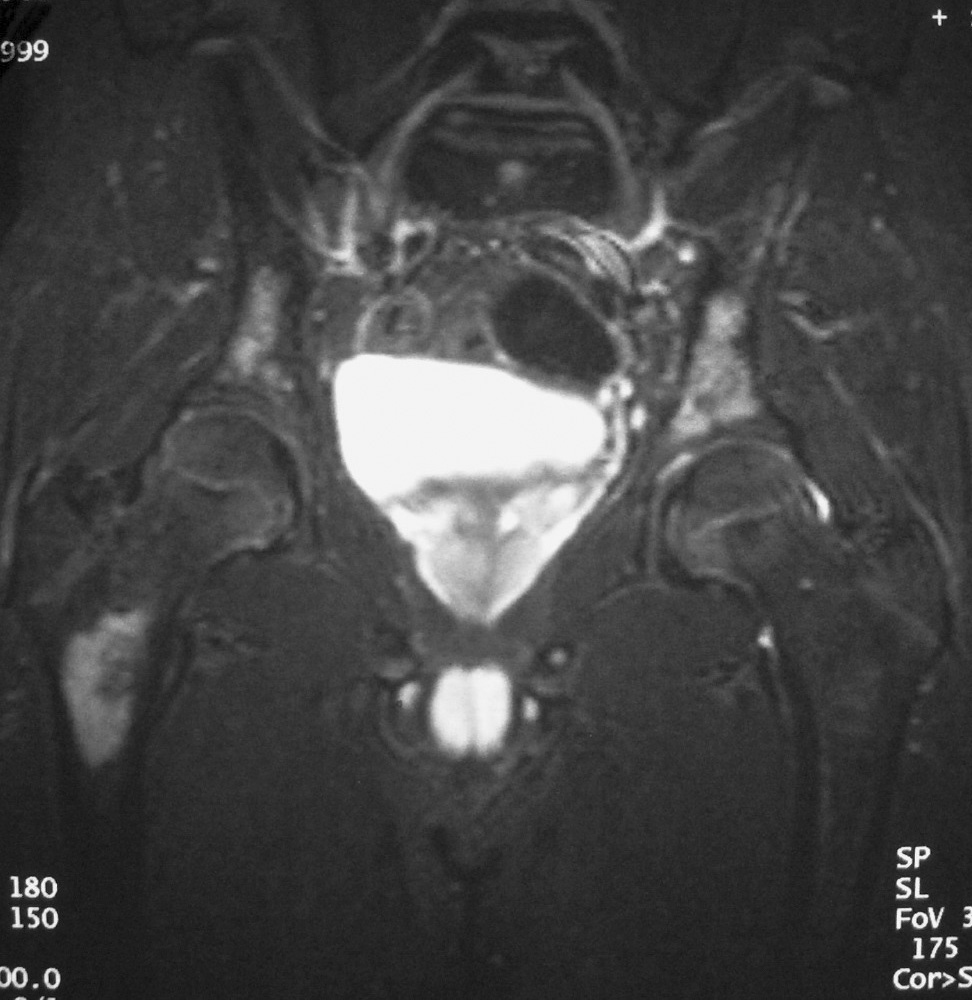

Fig. 10. Neuroblastoma intrarrenal. Niño de 9 años que presenta fiebre y dolor en la pierna izquierda. (A) Tomografía computarizada abdominal con contraste intravenoso. Masa intrarrenal sólida, con áreas necróticas, con mínimo parénquima circundante. (B) Resonancia magnética de control tras tratamiento con quimioterapia. Secuencia STIR. Cortes coronales de pelvis y ambas caderas. Lesiones hiperintensas en la medula ósea próxima a trocánter menor derecho, parte superior de hueso iliaco izquierdo y ambas regiones acetabulares.